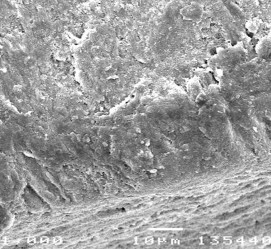

Hình ảnh mô học sau điều trị Enamel Pro varnish của sâu răng D1:

Hình 3.26: Hình ảnh bề mặt và mặt cắt ngang tổn thương sâu răng D1 sau điều trị bằng Enamel Pro varnish ở độ phóng đại 350 lần.

Hình 3.27: Hình ảnh mặt cắt ngang tổn thương sâu răng D1 sau điều trị bằng Enamel Pro varnish ở độ phóng đại 500 lần.

Hình 3.28: Hình ảnh mặt cắt ngang tổn thương sâu răng D1 sau điều trị bằng Enamel Pro varnish ở độ phóng đại 750 lần.

Hình 3.29: Hình ảnh bề mặt và mặt cắt ngang tổn thương sâu răng D1 sau điều trị bằng Enamel Pro varnish ở độ phóng đại 1000 lần.

Hình 3.30: Hình ảnh mặt cắt ngang tổn thương sâu răng D1 sau điều trị bằng Enamel Pro varnish ở độ phóng đại 1500 lần.